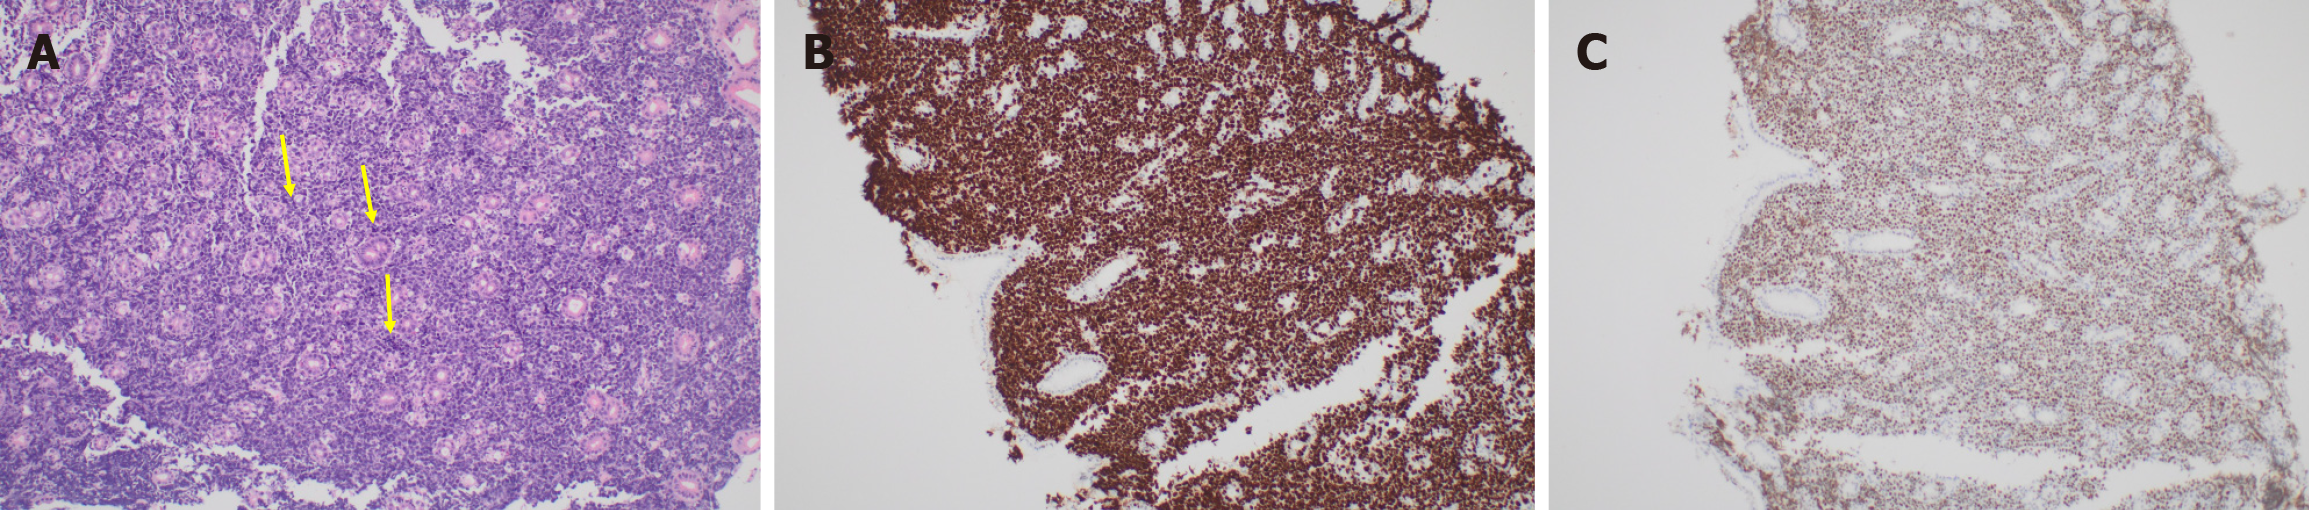

The histopathology from the gastric mucosal biopsies showed features that were initially suggestive of Burkitt’s lymphoma. There was diffuse infiltration by discohesive malignant cells that expanded the lamina propria and infiltrated between the glands. The neoplastic cells had a high nuclear/cytoplasmic ratio with hyperchromatic atypical nuclei, occasional prominent nucleoli and a limited amount of cytoplasm (Figure 3A). There was brisk mitotic activity with many abnormal forms. Ki67 was reported as 100% (Figure 3B). Immunohistochemical stains revealed that the neoplastic cells were CD20, CD19, CD10, BCL6 and c-MYC positive (Figure 3C). Negative stains included BCL2, CD3, CD5, CD21, Mum-1, CD30 and cyclin D1. No Helicobacter pylori microorganisms were identified on immunohistochemical stain. Further FISH analysis showed MYC and BCL6 rearrangement with a lack of IgH/MYC rearrangement, which is specific for Burkitt’s lymphoma. Hence, the favoured diagnosis was high-grade “double-hit” B-cell lymphoma with MYC and BCL6 rearrangements.